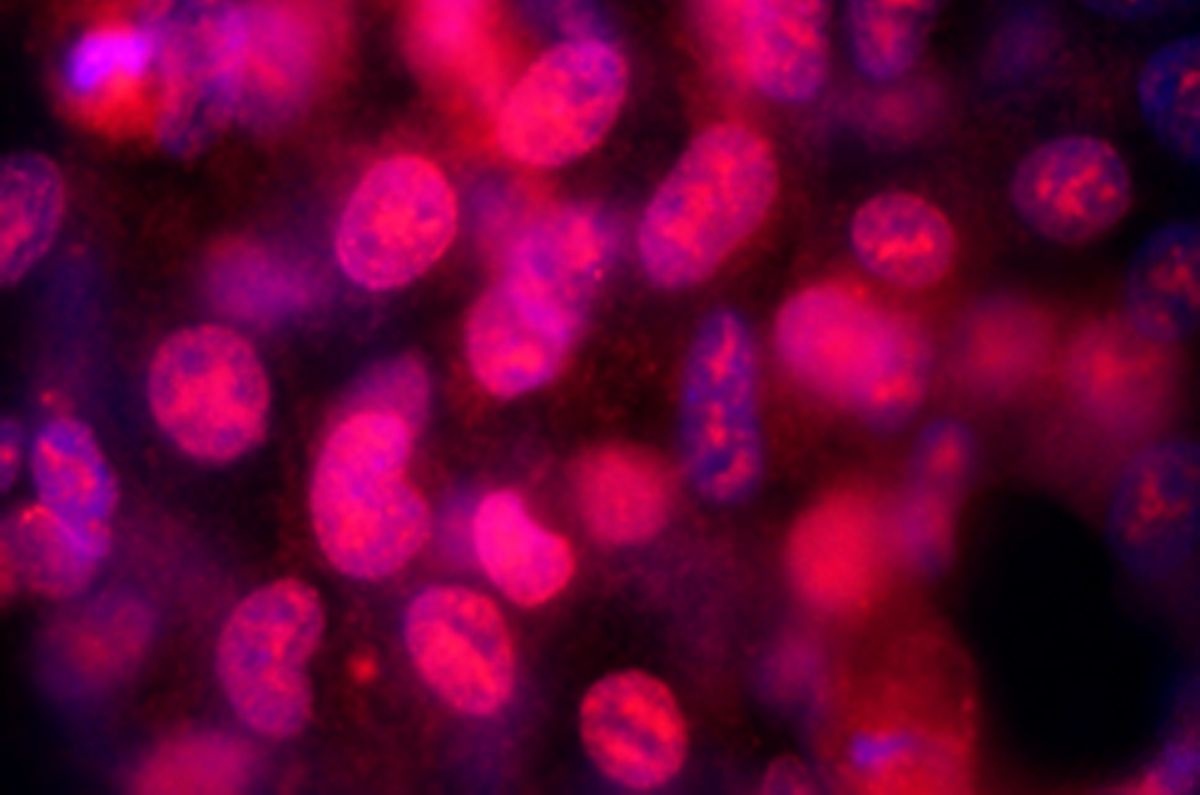

Az Általános Orvostudományi Kar Anatómiai, Szövet- és Fejlődéstani Intézet Jelátviteli Kutatócsoportja a készülék ötletgazdájaként a működési elv kidolgozása során azt a cél fogalmazta meg, hogy a műszer szimulálni tudja a vázrendszert a járás és a futás során érő mechanikai ingereket. A készülék alkalmas lesz bármilyen, folyadékkal körülvett sejtféleség ingerlésére, úgy mint a csontsejtek, az izomsejtek, a kötőszöveti sejtek, a hámsejtek vagy akár a differenciálatlan őssejtek, a kitapadó daganatsejtek, illetve a differenciálódó sejtkultúrák.